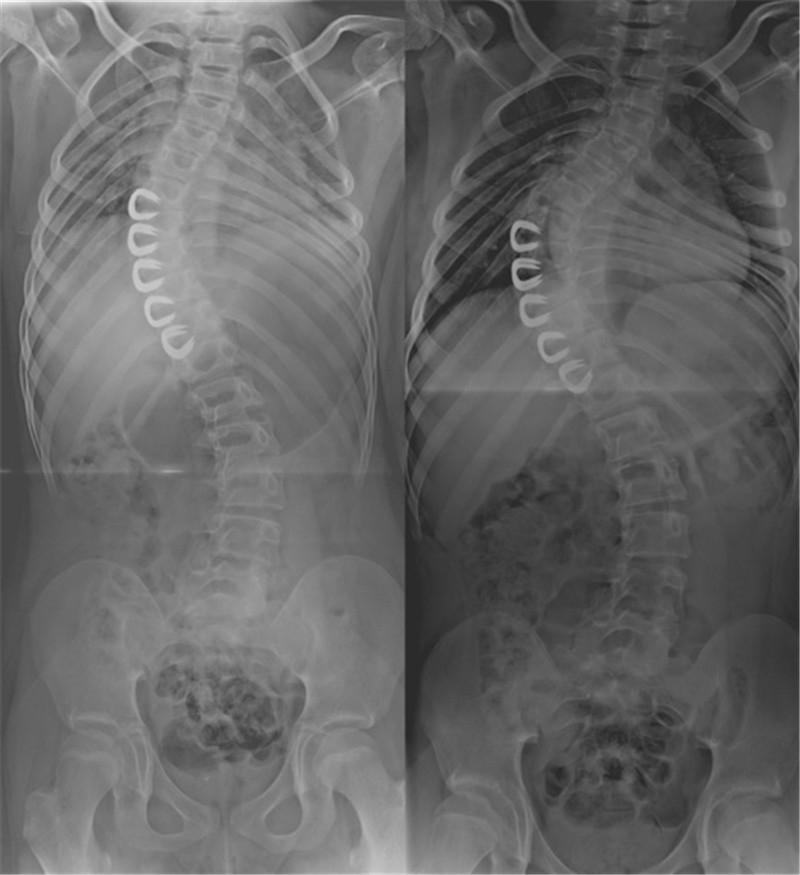

2012年,Akbarnia等[8]报道了MCGR的动物实验及初步临床结果(图 5),实验动物研究中,磁力控制生长棒(magnetically controlled growing rod, MCGR)最终延长达预期80%,且未发现相关并发症。2013年Akbarnia[9]再次报道了14例临床初步结果(图 2 右),平均随访10个月(5.8-18.2),未观察到相关严重并发症,其结果初步验证了其安全性。MCGR相关研究随之成为热点。